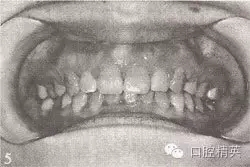

參見圖9-33 雙側(cè)后牙鎖頜矯治前后

A.雙側(cè)后牙鎖頜矯治前

B.雙側(cè)后牙鎖頜矯治后